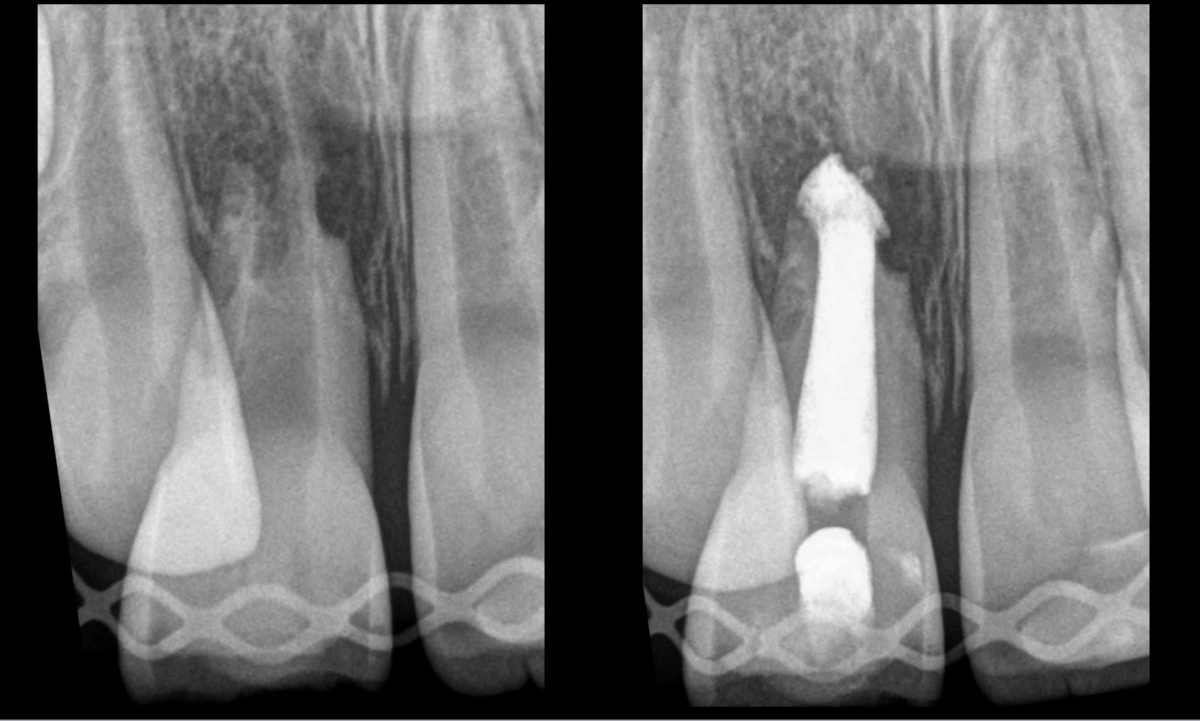

➡️ 𝐓𝐫𝐚𝐢𝐭𝐞𝐦𝐞𝐧𝐭 𝐜𝐚𝐧𝐚𝐥𝐚𝐢𝐫𝐞 𝐫𝐞́𝐚𝐥𝐢𝐬𝐞́ 𝐚𝐯𝐞𝐜 𝐮𝐧𝐞 𝐬𝐞́𝐚𝐧𝐜𝐞 𝐝’𝐡𝐲𝐝𝐫𝐨𝐱𝐲𝐝𝐞 𝐝𝐞 𝐜𝐚𝐥𝐜𝐢𝐮𝐦.

Auriez-vous réalisé une revitalisation sur cette dent permanente immature ❓